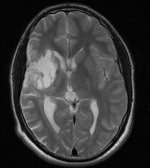

Meine MRT

Aufnahmen:

T2-gewichtetes MRT |

Organisches Gewebe enthält viel Wasser und Fett. Diese Stoffe

bestehen im Mensch aus ca. 63% Protonen. Setzt man Protonen einem

magnetischen Feld aus, schwingen sie entsprechend der Feldstärke.

Diese absorbierte Energie geben sie wieder ab, was man messen kann.

Die Signalstärke wird durch jedes Proton leicht variiert.

Läßt

man ein zusätzliches Magnetfeld einwirken, das in Stärke und Lage

variiert wird, läßt sich durch die unterschiedliche Resonanz der

Felder pro Ort eine elektromagnetische Strahlung messen. Daraus kann

man ein 3D-Bild berechnen.